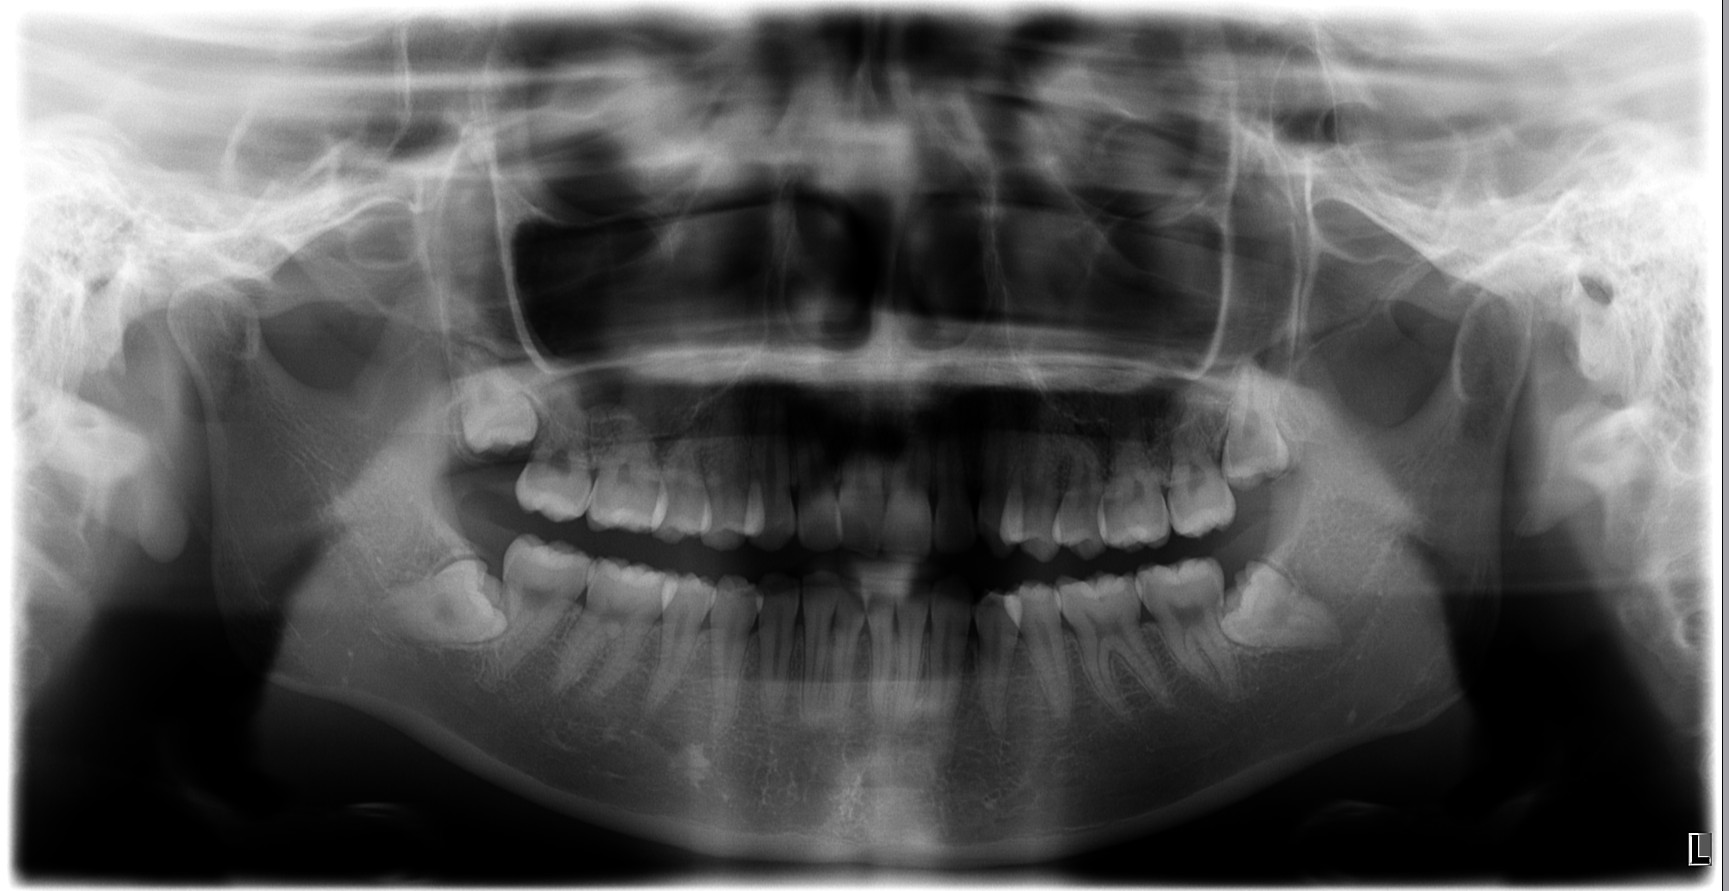

治療前

パノラマX線写真で、上下とも下顎管および上顎洞との近接が確認されました。

(※以下の画像は実際の術前・術後のパノラマ写真を掲載)